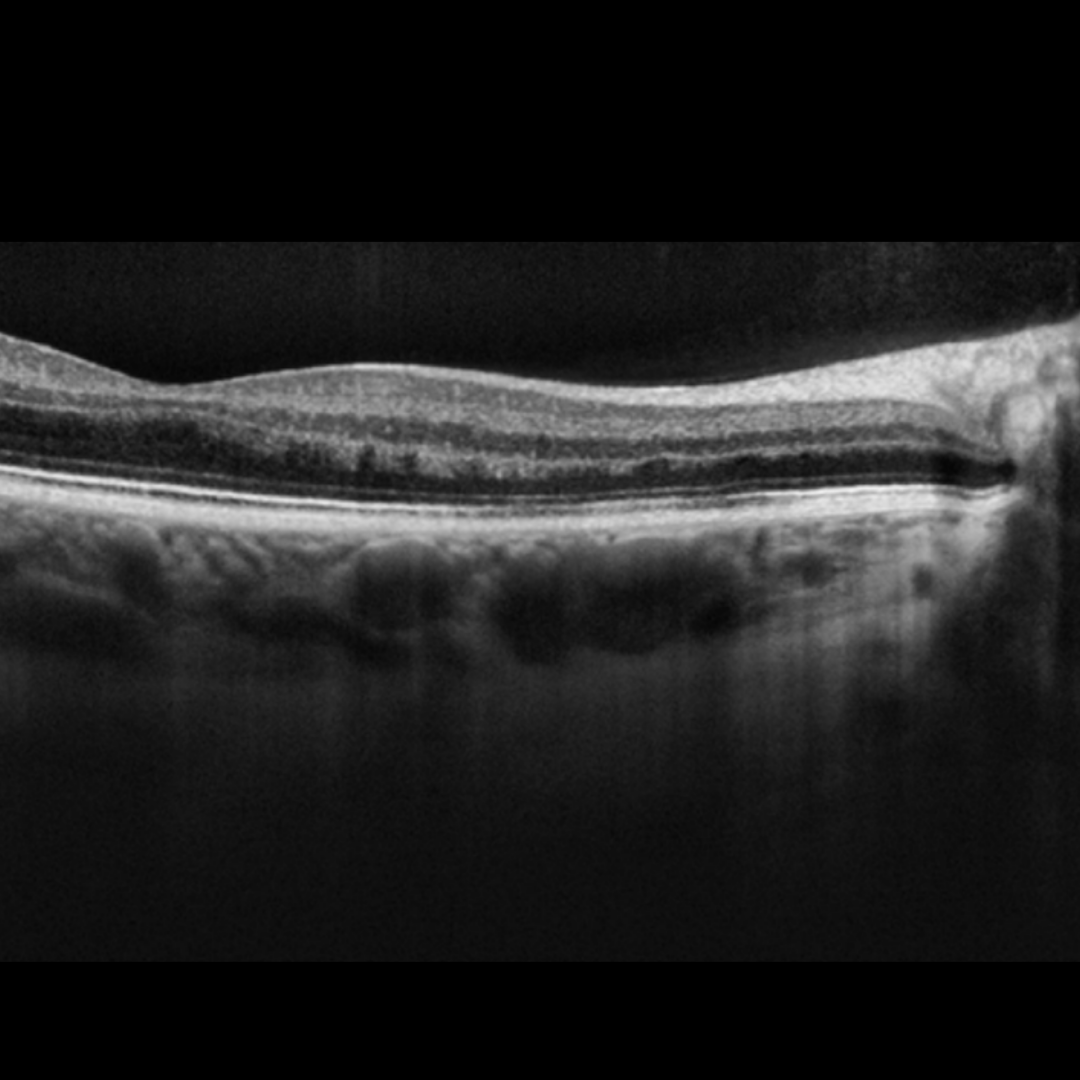

OCT imaging through the lesions usually show disruption of the outer retina.

More infoCirrus OCT macular line scans (right - top, left - bottom)